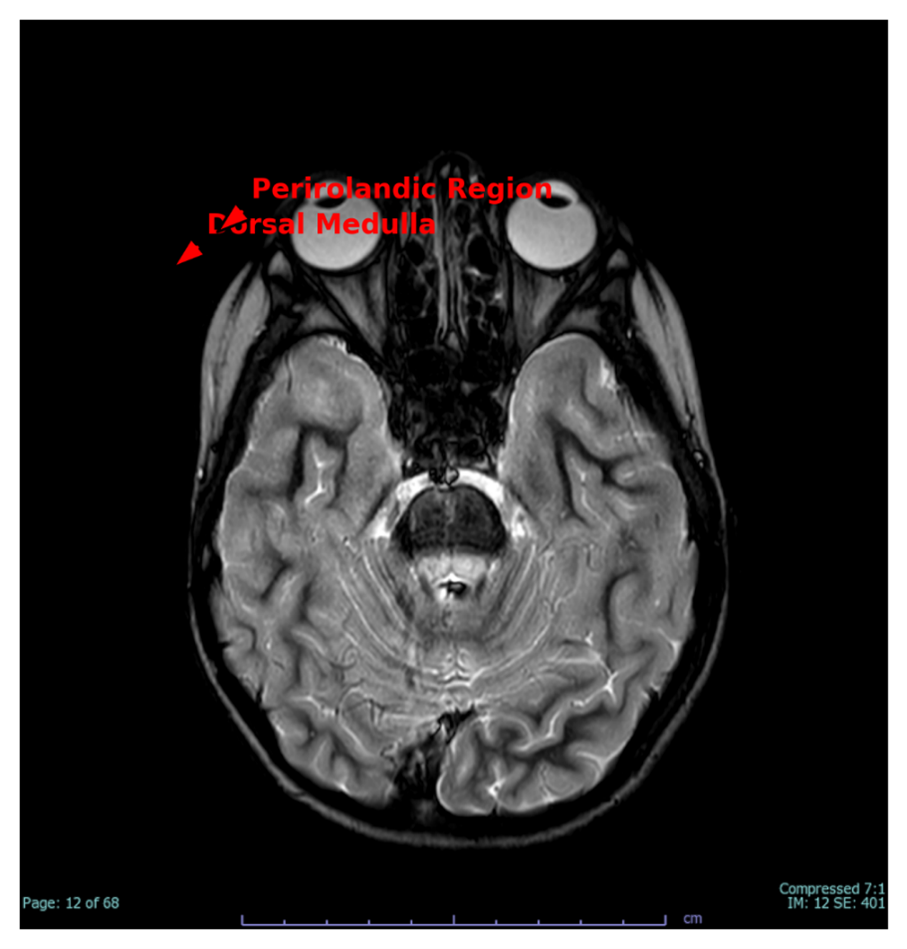

Figure 3 demonstrates dorsal medulla signal alterations and volume loss in the perirolandic area, perhaps indicating a mixture of progressive mitochondrial degeneration and a distant perinatal hypoxic injury. These abnormalities correlate with the patient's dysautonomia, fine motor weakness, and evidence of pyramidal tract dysfunction.

Figure 3. Axial T2-weighted image revealing hyperintensity at the dorsal medulla and loss of perirolandic white matter (red arrows), indicative of chronic mitochondrial injury and distant hypoxic damage.